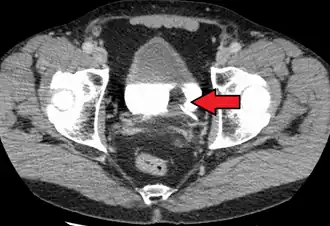

| Carcinoma de células de transição. O branco na bexiga é o contraste. | |